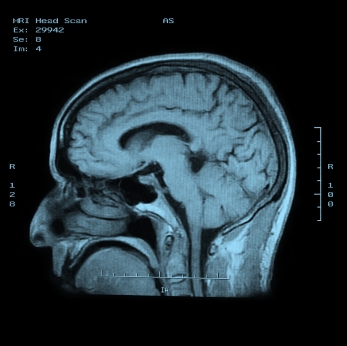

Врач собирает анамнез болезни, выслушивает и изучает жалобы больного, назначает лабораторные и инструментальные исследования: МРТ, исследование электрической активности мозга (измерение вызванных потенциалов), спинномозговая пункция, исследование спинномозговой жидкости.

Медицинские процедуры, проводимые при заболевании рассеянный склероз: Консультация невропатолога, Консультация офтальмолога, Спиральная компьютерная томография, Магнитно-резонансная томография, Спинальная пункция, Исследование спинномозговой жидкости